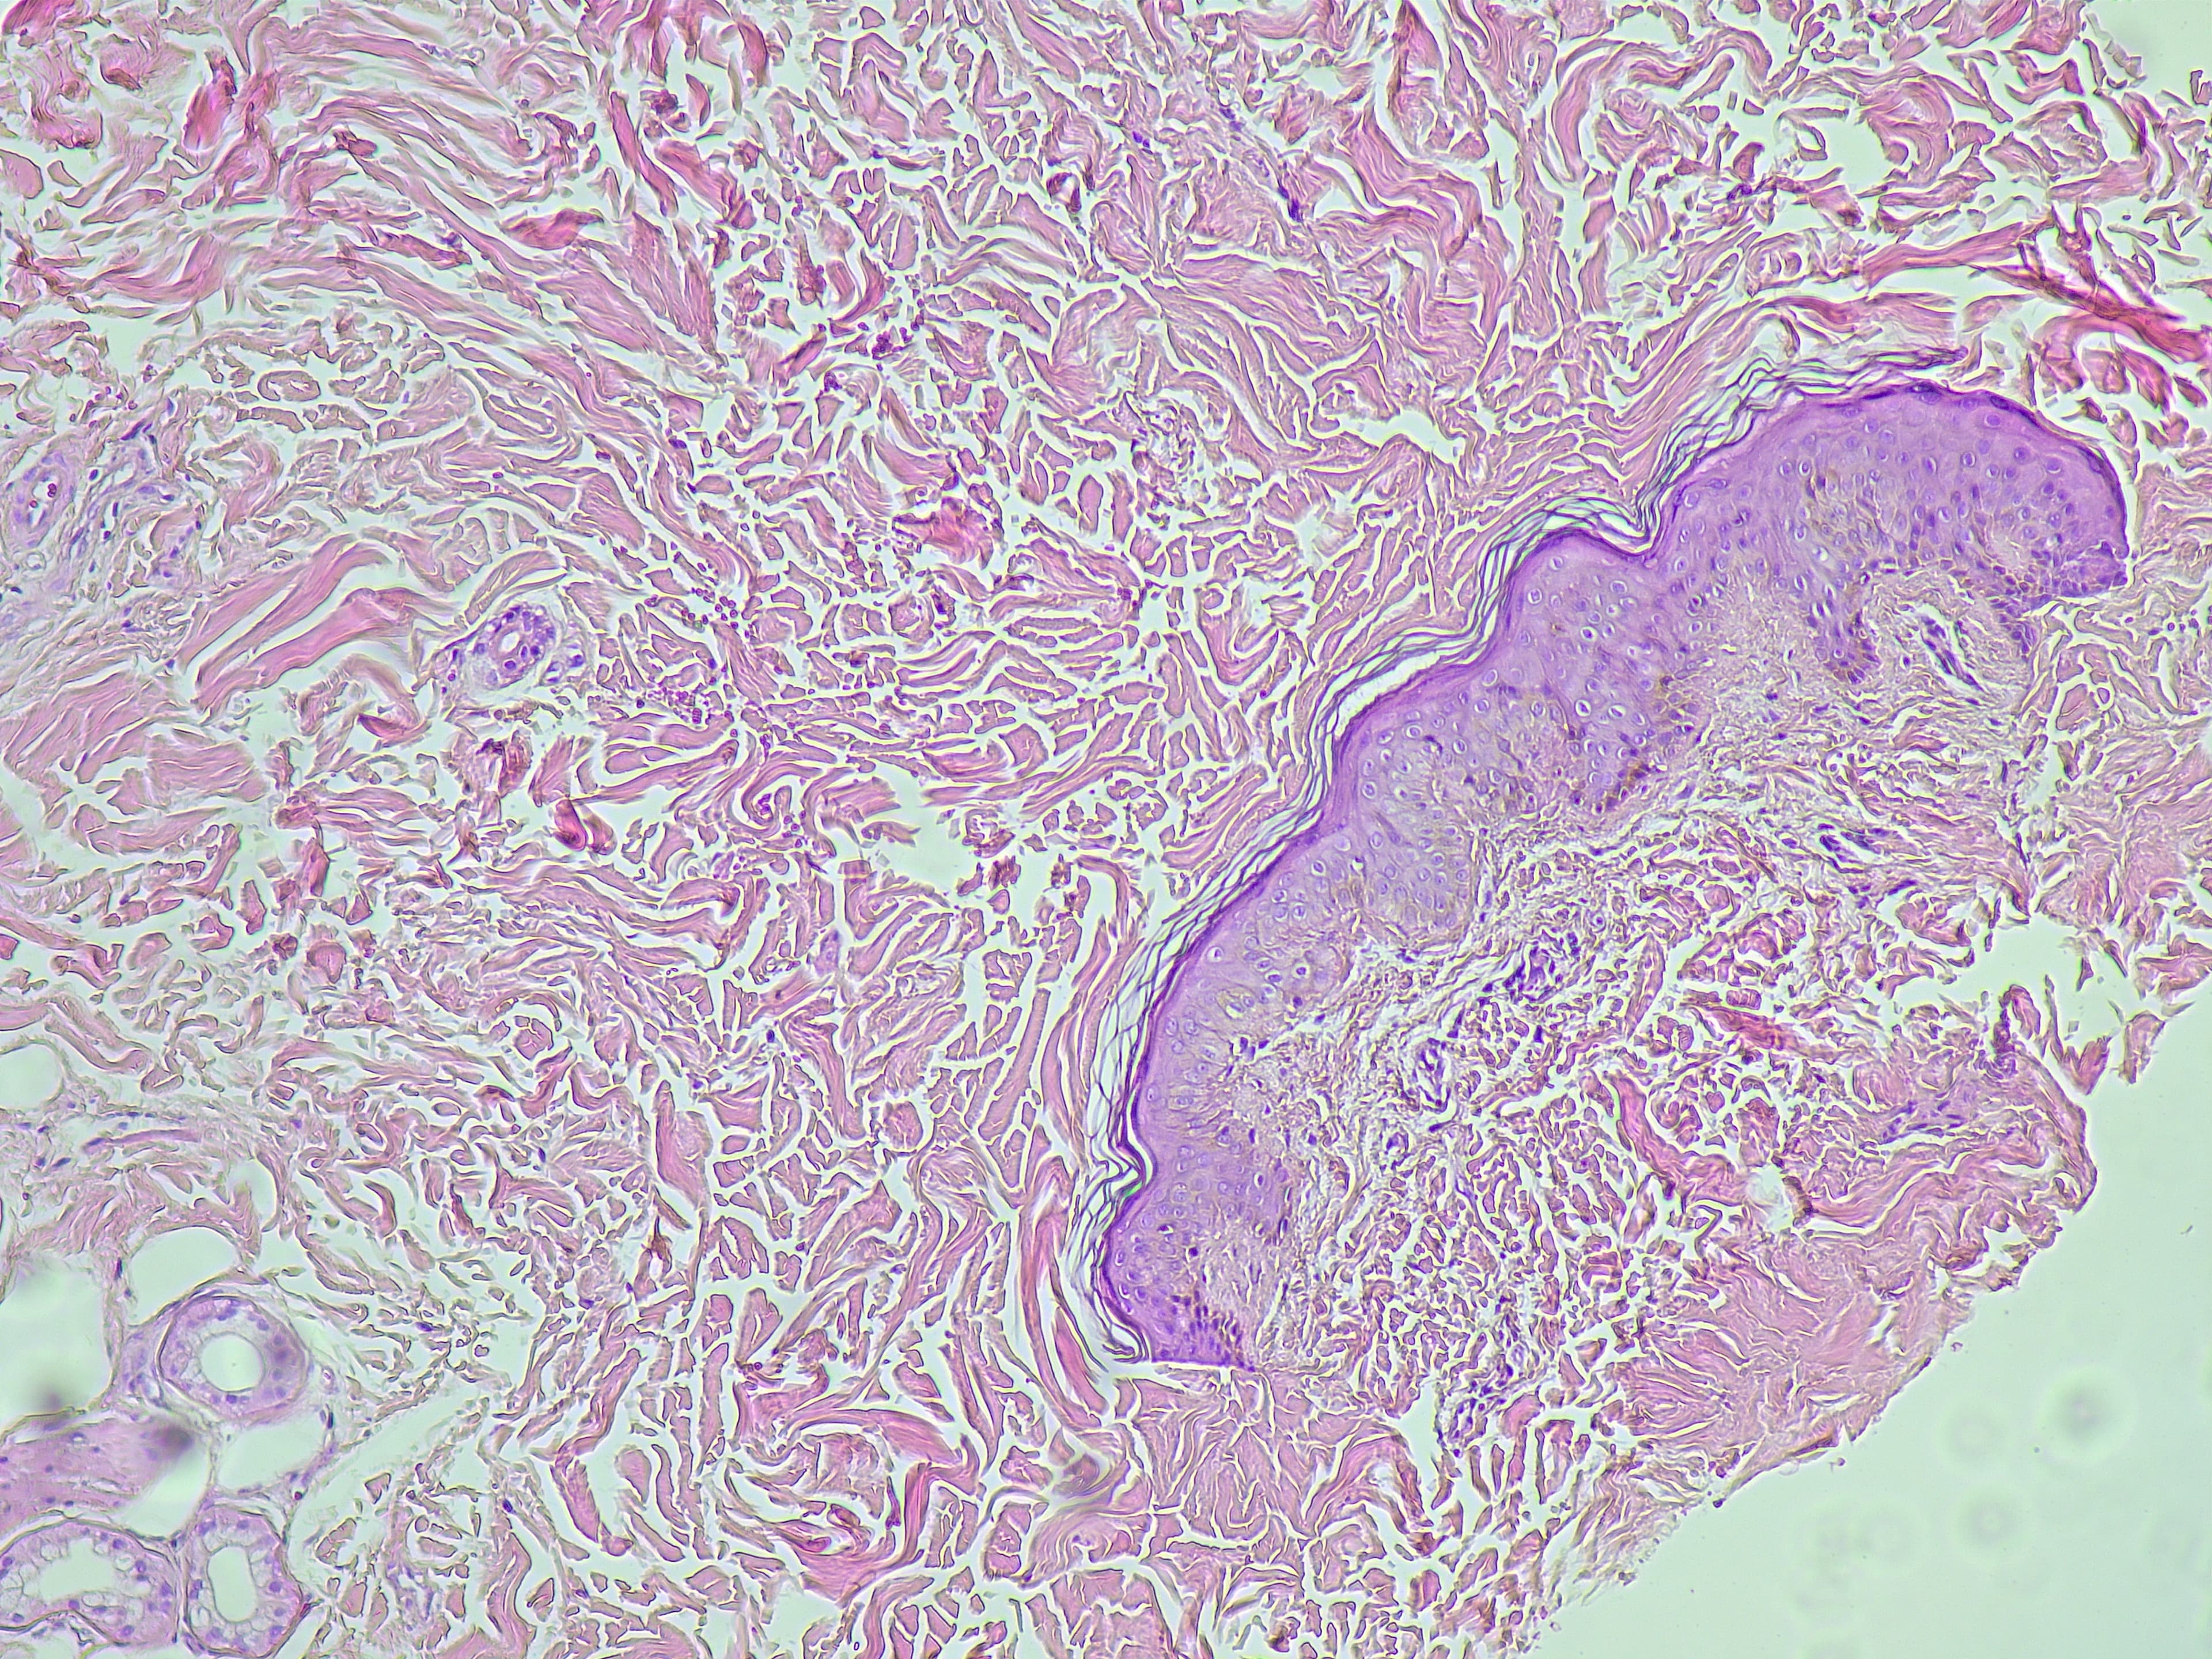

- Hautbiopsie – Entnahme und Analyse einer kleinen Gewebeprobe im Labor.

Wie Dermatologen BCC diagnostizieren

Unsere Dermatologen nutzen moderne Diagnoseverfahren zur Beurteilung von Hautveränderungen und zur Bestätigung eines BCC. Zu den Methoden gehören:

- Dermatoskopie – Vergrößerte Hautuntersuchung zur Beurteilung von Strukturen und Mustern.